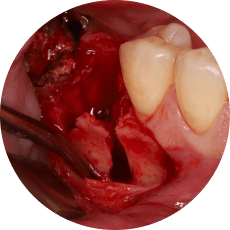

Методика удаления зубов в боковом сегменте верхней челюсти

Что будет в модуле:

Атравматичное удаление премоляров и моляров верхней челюсти

Инструменты и четкие правила удаления

Осложнения: ороантральное сообщение, попадание корня в пазуху

От простого удаления щипцами до фрагментации бором - вы приобретете уверенные навыки в боковом сегменте верхней челюсти, включая работу с осложнениями.